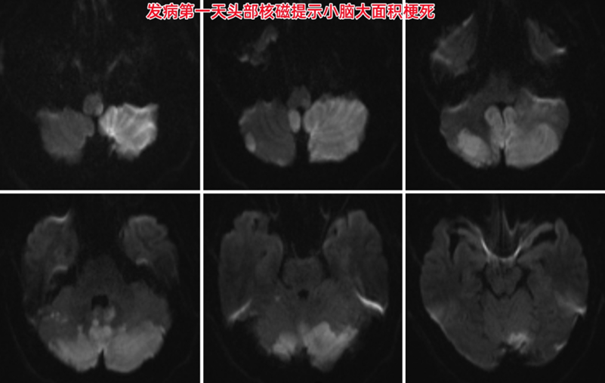

春节期间,40岁的小王起床后出现头晕、恶心,他以为是昨晚酒喝多了,也没在意,就在家里睡觉休息,但直到第二天上午头晕还是很严重,家人发现他说话也越来越不清楚,这才赶紧打120救护车到医院就诊。到了泰达医院急诊室,头CT检查发现双侧小脑和大脑后枕部都已经缺血显影,经脑血管病绿色通道行头部核磁与脑血管成像检查,提示双侧小脑、脑干及枕叶急性脑梗死,椎基底动脉闭塞。